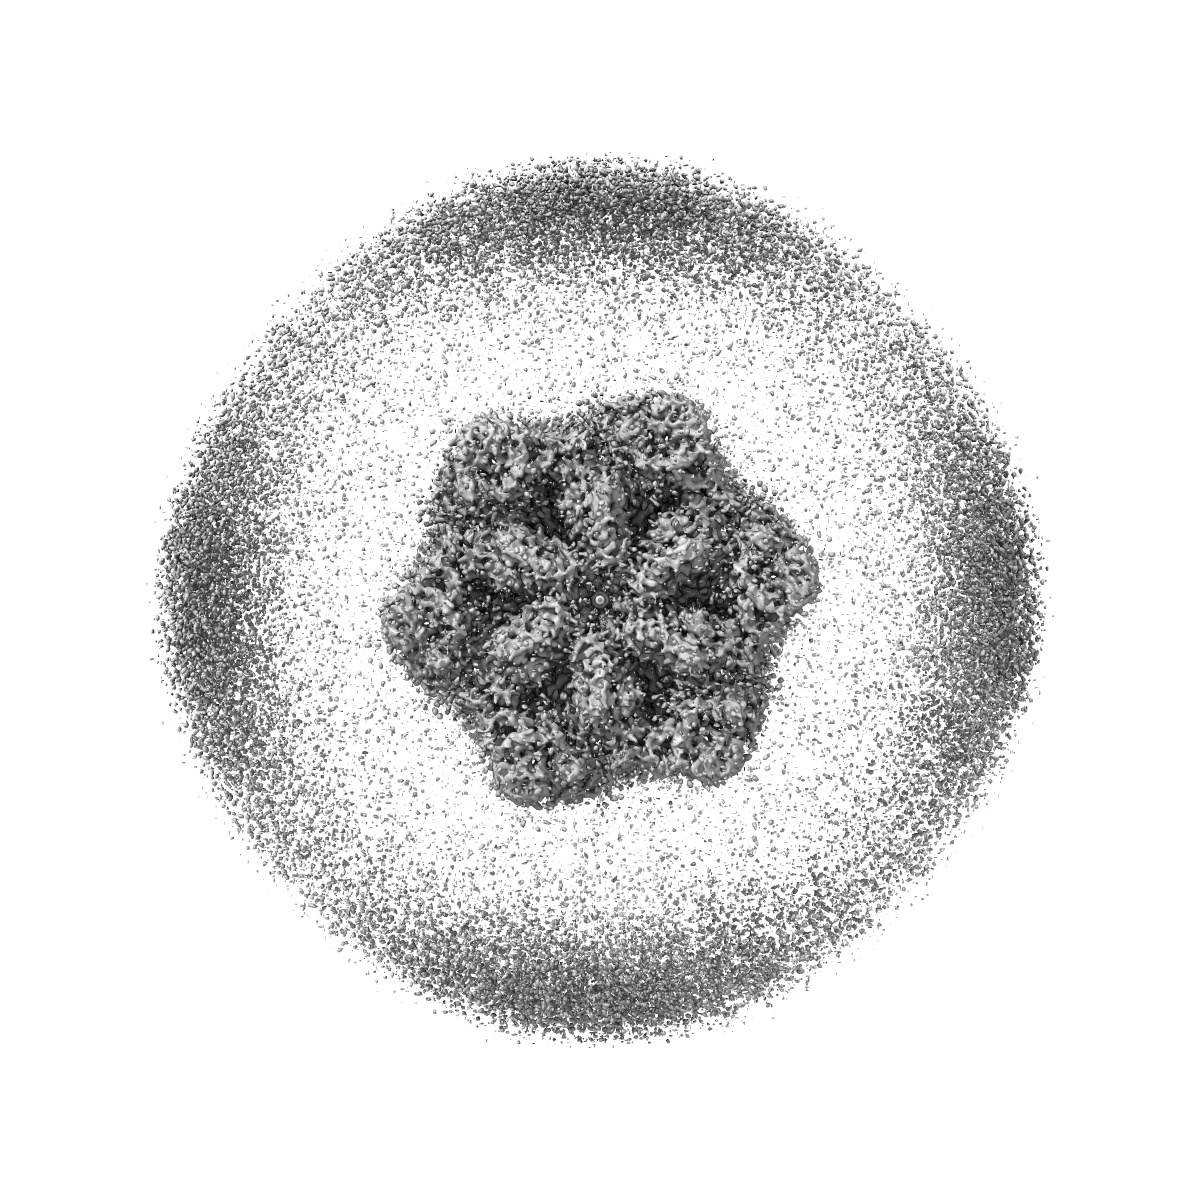

Human p97/VCP structure with a triazole inhibitor (NSC799462/dodecamer)

Single-particle3.33 Å

Sample: p97/VCP AAA+ ATPase/NSC799462

Mechanism of allosteric inhibition of human p97/VCP ATPase and its disease mutant by triazole inhibitors.